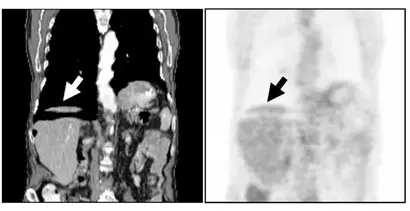

下圖是 PET/CT 影像,箭頭所指的影像假影是什麼原因造成?

- 左圖(CT 冠狀面影像):白色箭頭指向右側橫膈膜與肝臟圓頂(Liver dome)處。可以觀察到肝臟頂部與肝臟主體之間,出現了不自然的低密度空隙或雙重輪廓。這在臨床上被稱為「浮動肝臟(Floating liver)」現象,是因 CT 掃描過程中呼吸運動或與 PET 呼吸狀態不匹配所造成的典型特徵。

- 右圖(PET 冠狀面影像):黑色箭頭指向與 CT 影像相對應的肝臟頂部,此處出現了一個新月形(Curvilinear)的放射性活性減低區(Cold artifact/冷假影)。